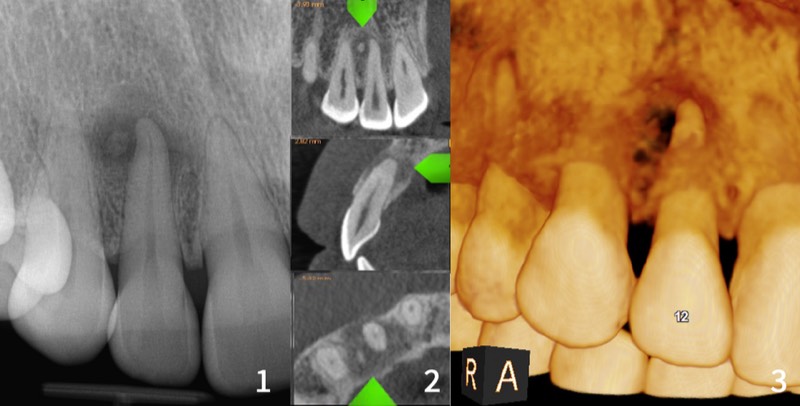

PRP (Platelet-Rich Plasma) tedavisi, hastanın kendi kanından elde edilen büyüme faktörlerinin konsantre formunun cilt, saç derisi veya doku içine enjekte edilmesiyle doğal rejenerasyonu hızlandıran ileri bir biyolojik tedavidir. Tamamen doğal, güvenli ve alerjik risk yoktur.Trombositler PDGF, TGF-β, VEGF, EGF ve FGF gibi güçlü büyüme faktörleri içerir. Hücre çoğalmasını, kolajen sentezini, yeni damar oluşumunu ve doku onarımını tetikler.Dentaline'de steril koşullarda hazırlanır: 10-20 ml kan alınır, santrifüj edilir, PRP tabakası ayrıştırılır.Cilt gençleştirme (vampir yüz bakımı): kolajen ve elastin üretimini artırır, ince çizgiler azalır, cilt sıkılaşır, gözenekler küçülür. Yüz, boyun, dekolte, el sırtına uygulanır.Saç dökülmesi tedavisi: kıl foliküllerini besler, anagen fazını uzatır, dökülmeyi azaltır, yeni büyümeyi tetikler. Androgenetik alopesi, stres, postpartum dökülmede etkili.Diş hekimliğinde: implant sonrası iyileşme, kemik grefti entegrasyonu, periodontal rejenerasyon. Antimikrobiyal özellikler enfeksiyon riskini azaltır.3-4 seans, 2-4 hafta arayla. Cilt sonuçları 2-3 haftada, saç 3-6 ayda görülür. Yılda 1-2 idame seansı. Kontrendikasyonlar: hamilelik, aktif enfeksiyon, kan hastalıkları.